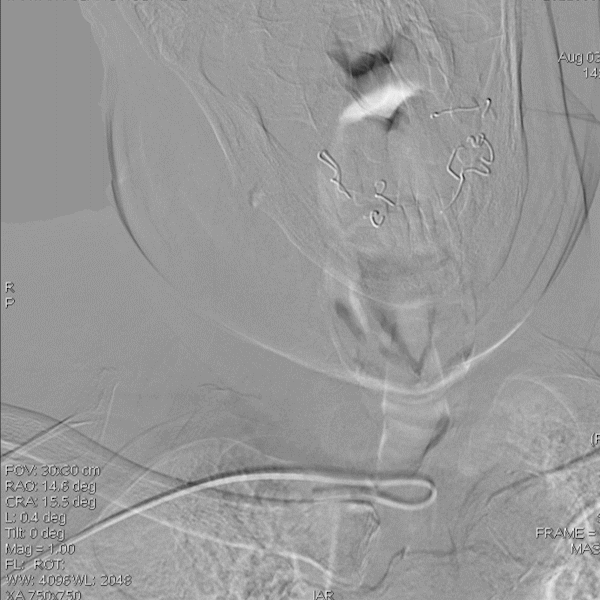

病变情况分析:右桡动脉穿刺,置6F桡动脉鞘管,5F多功能导管在泥鳅导丝辅助下脑血管造影提示:右椎动脉V4段重度狭窄(约90%)。

泥鳅导丝携5F 115cm颅内支撑导管,至右椎动脉V2段。

在颅内支撑导管支撑下,将0.014'' 300cm微导丝,通过狭窄节段将其放置在基底动脉中段。将2.0mm*10mm球囊打起预扩狭窄部位,然后更换赛诺神畅 颅内药物洗脱支架NOVA DES® 2.5*10mm延微导丝顺利通过狭窄节段,再次造影见定位准确,缓慢扩张球囊释放支架。